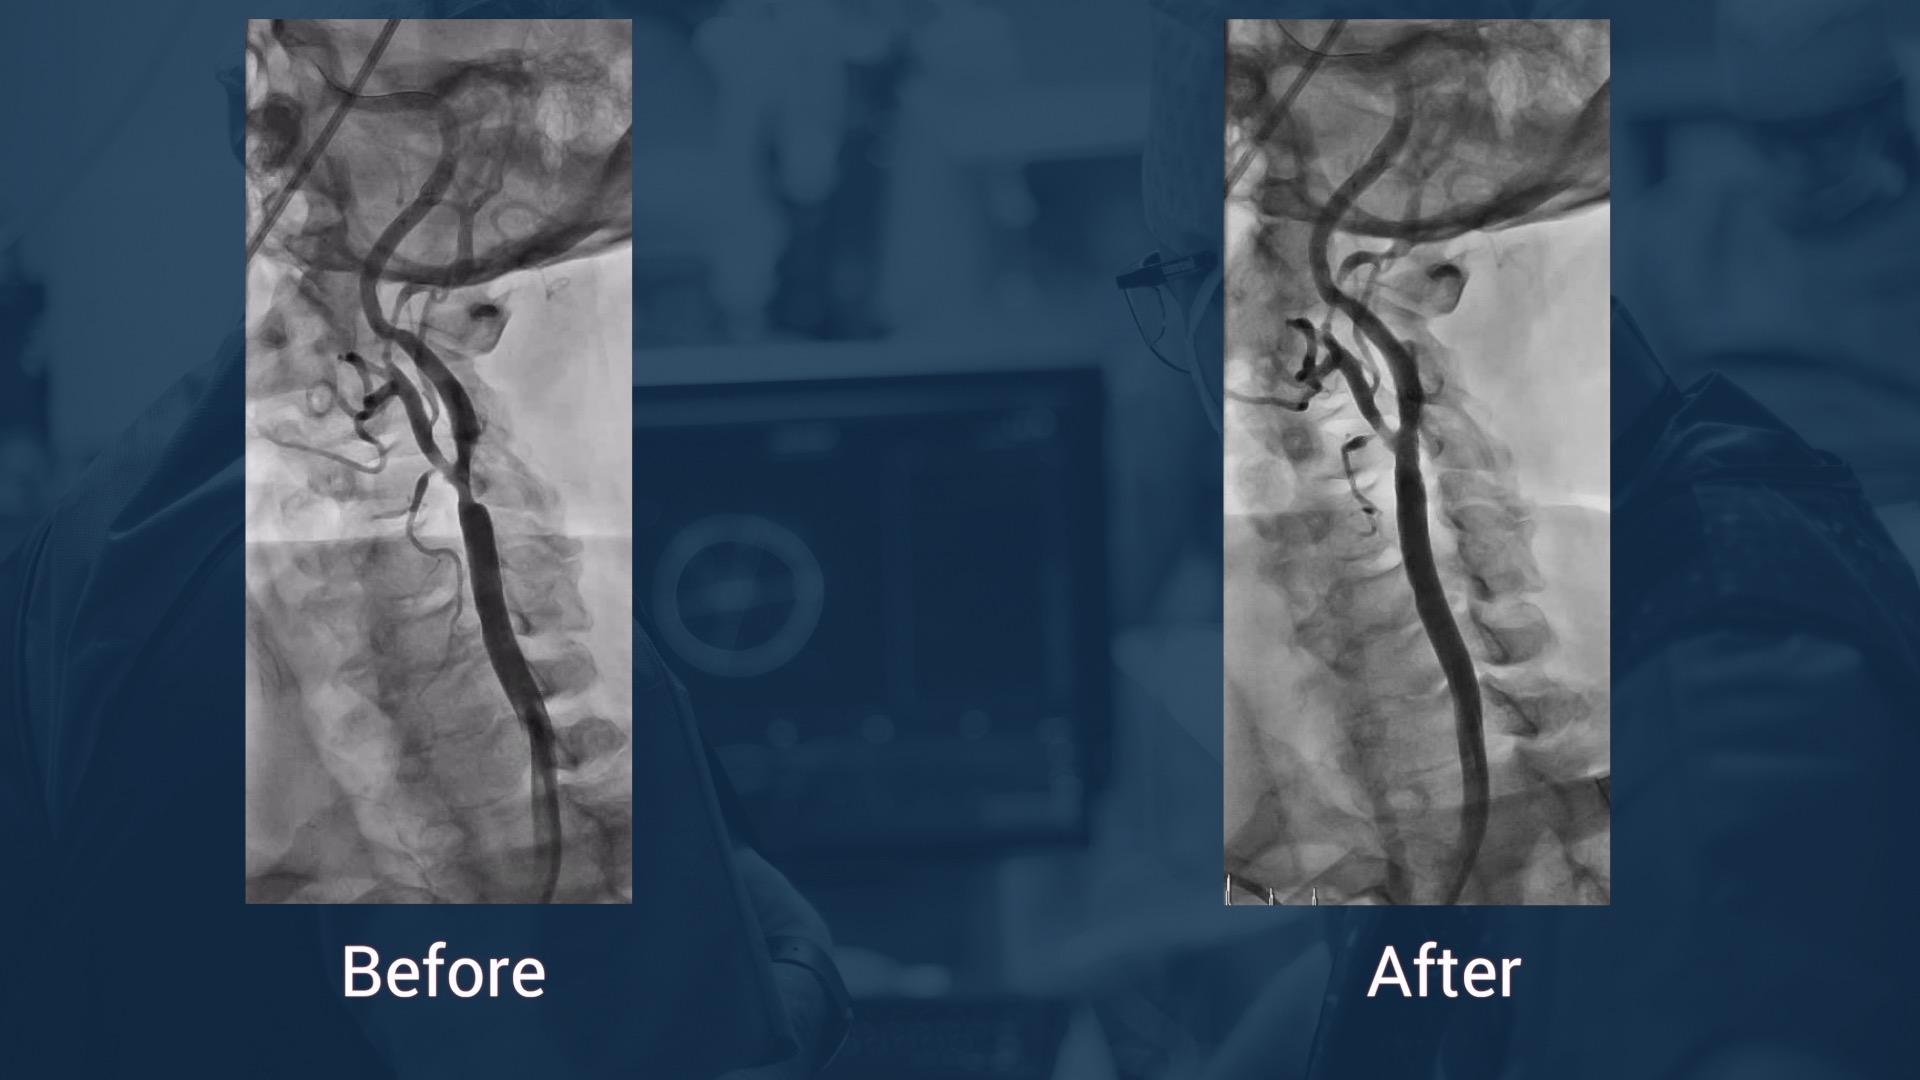

Carotid procedures: Improve your skills!

Improve your skills on carotid artery stenting procedures! You will be able to learn more about carotid artery access: femoral, brachial, radial.  Learn about carotid artery protection dur...